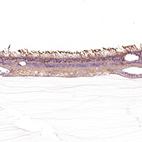

Immunohistochemical staining of human colon, eye, retina, liver and lymph node using Anti-GRK1 antibody HPA035200 (A) shows similar protein distribution across tissues to independent antibody HPA059376 (B).